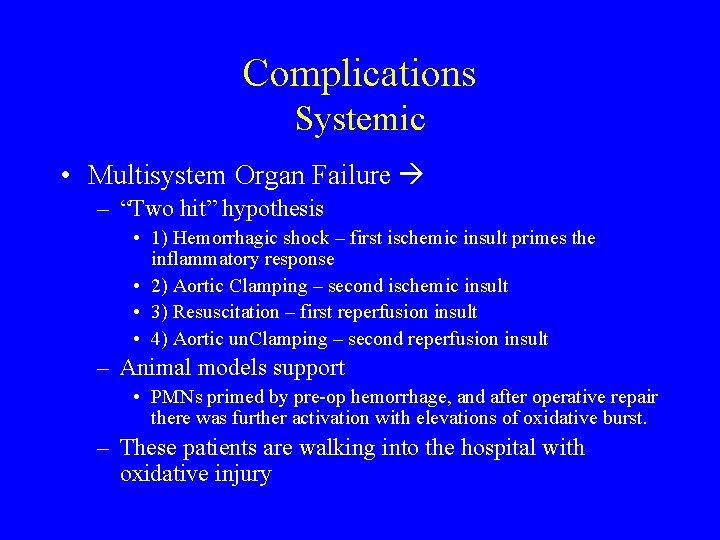

Complications Systemic • Multisystem Organ Failure – “Two hit” hypothesis • 1) Hemorrhagic shock – first ischemic insult primes the inflammatory response • 2) Aortic Clamping – second ischemic insult • 3) Resuscitation – first reperfusion insult • 4) Aortic un. Clamping – second reperfusion insult – Animal models support • PMNs primed by pre-op hemorrhage, and after operative repair there was further activation with elevations of oxidative burst. – These patients are walking into the hospital with oxidative injury